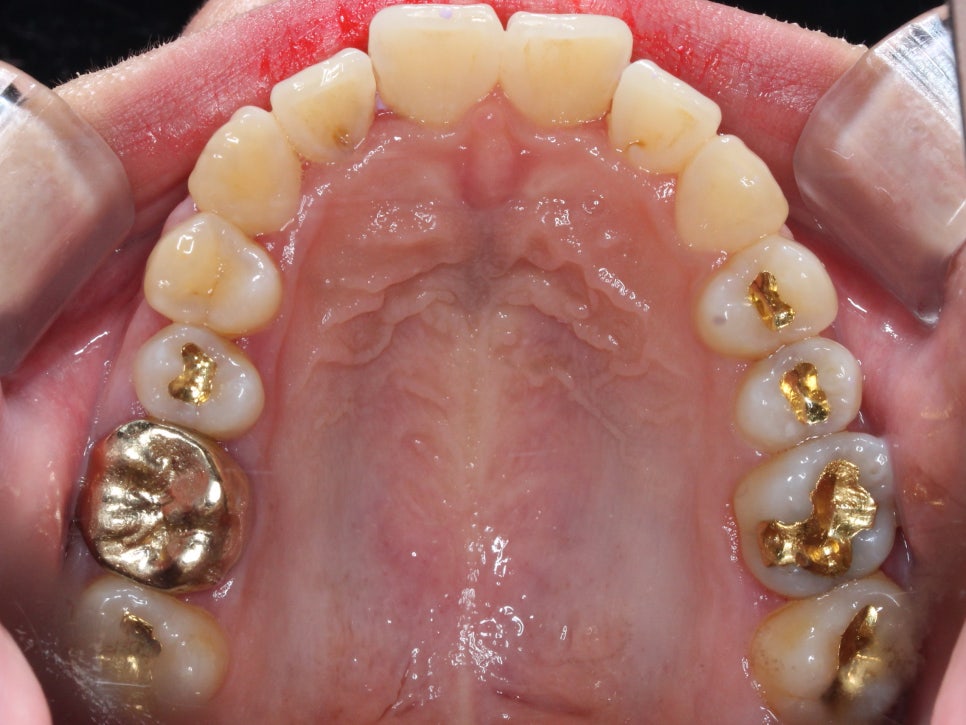

첫 방문

처음 방문 하셨을 때 모습입니다.

윗니가 전체적으로 삐뚤빼뚤한 것이 보입니다.

잘 보이실진 모르겠지만,

우측 구치부는 전반적으로

거꾸로 물리는 양상이 보입니다.

(사진상 왼쪽)

중간과정

우선 배열을 바로 잡기로 했습니다.

치아를 가지런하게 펴기 위해선

치간삭제는 필수적이었습니다.

삭제 없이 치아를 펴면

뻐드러지기 때문에

치아에 해를 끼치지 않는 선에서

치간삭제를 시행합니다.